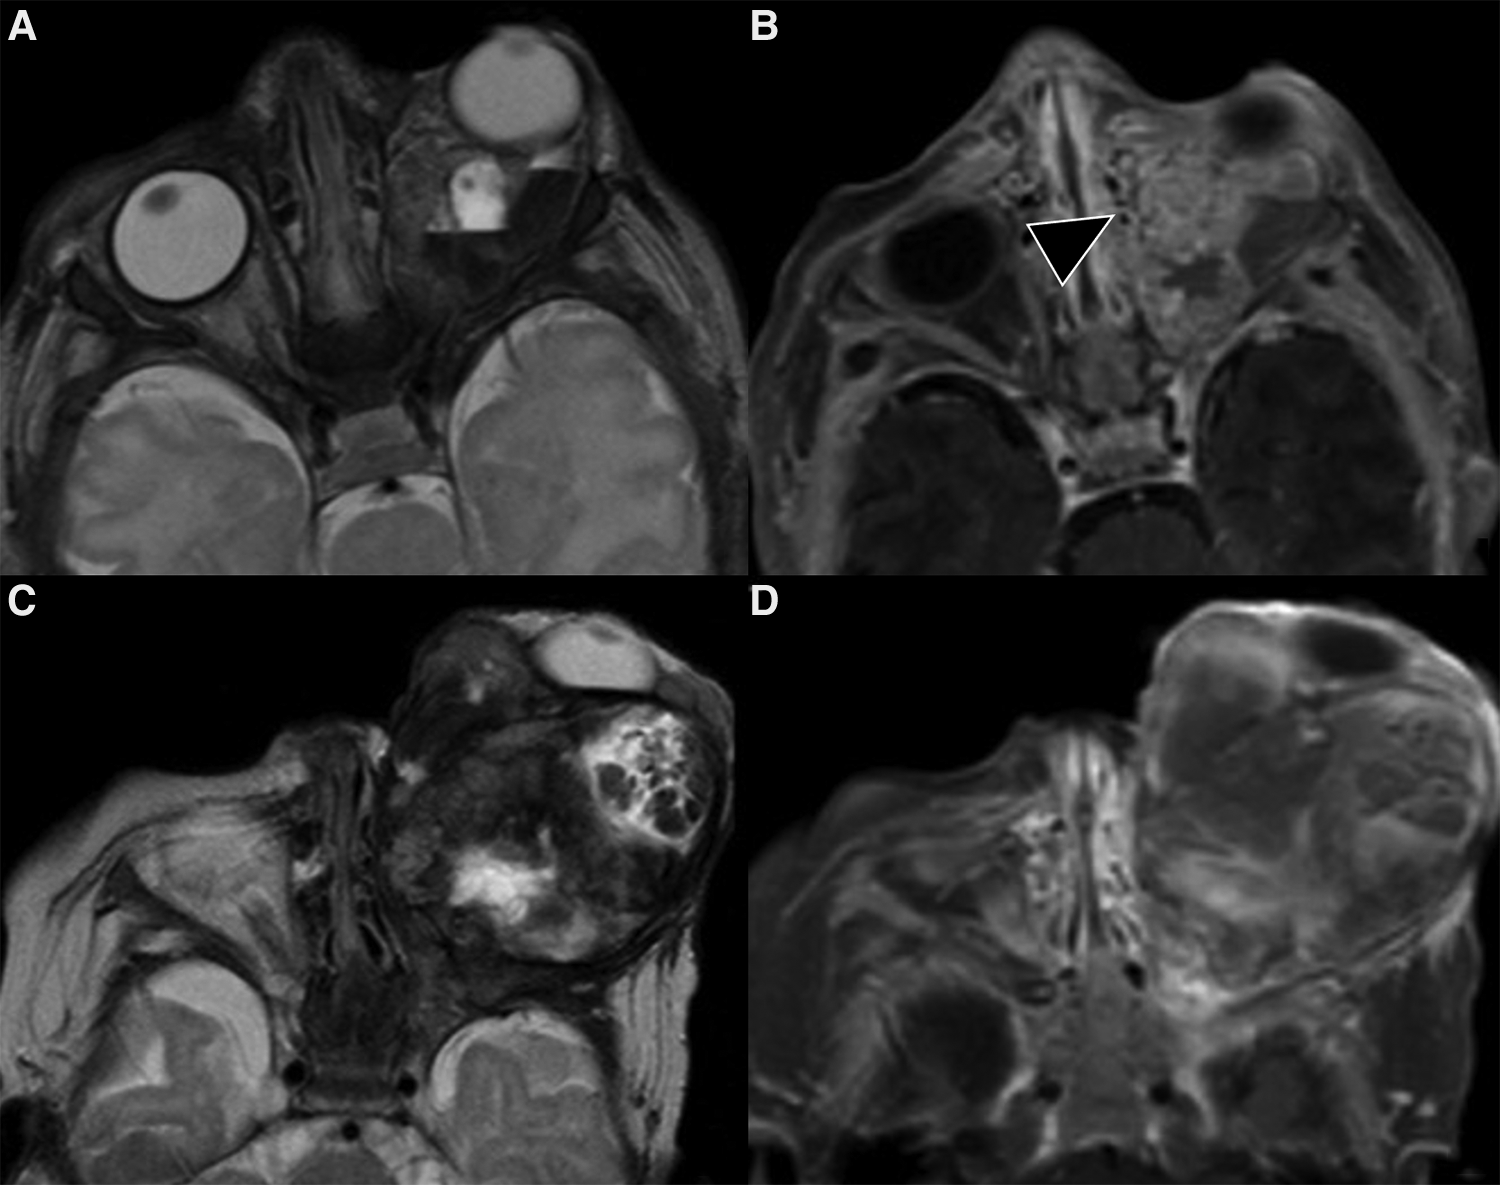

On the other hand, it is MRI that provides the best insights on the architecture and the best accuracy on the extension and spatial relationships of the lesion. Indeed, it may show the tumor involving and enlarging the eyelid and obstructing vision, displacing or distorting the globe or the extra- ocular muscles. On T2w images hemangiomas appear as a well-defined, lobulated and hyperintense masses with flow-voids and thin, dark septa between lobules (Figure 4). These features are even more striking on STIR images (Figure 4). Flow voids are less likely seen in the involuting and involuted phase. On T1w sequences they show a heterogeneous low/intermediate signal with a variable amount of hyperintensity related to fat tissue deposits according to the evolutionary phase. Contrast enhancement is usually homogeneous and intense during the proliferative phase (Figures 4, 5), although it may become less homogenous, intense and predictable in the involuting and involuted phase.

Figure 4. Mr images of a non-syndromic left periorbital infantile hemangioma in a 1-year-old girl. Axial (A) and coronal fat-saturated (B) T2 weight images show a well-defined hyperintense mass (arrow in A) with multiple internal flow voids (black arrowheads in B and D), extending from the anterior periorbital soft tissues into the extra and intraconal compartments of the orbit. Axial (C) and coronal (D) contrast-enhanced fat-saturated T1 weighted images show vivid homogeneous contrast enhancement of the vascular lesion.

Figure 5. Mr images of a 6-month-old girl with known PHACES. Axial T2 (A) and contrast-enhanced T1 weighted images (B,C) show a diffuse segmental hemangioma of the right orbital, malar and auricular regions. Coronal dynamic MR angiography during gadolinium injection (D–F) shows the “progressive filling” of the vascular lesion. Also note in (C) the small enhancing mass in the right internal auditory canal (white arrow), consistent with an intracranial hemangioma, and the ipsilateral cerebellar hypoplasia.

It includes: Posterior fossa abnormalities (Dandy-Walker or cerebellar hypoplasia usually on the same side of the hemangioma) (Figures 5, 6), Hemangioma, Arterial abnormalities (Figure 6), Cardiac anomalies (coarctation of the aorta), Eye defects and Sternal abnormalities (24). Importantly, cerebral arterial abnormalities are the most frequently associated abnormalities in the literature (25) and they are usually located on the same side of the IH and cerebellar findings, supporting the embryological pathogenesis (26). Hence, all patients with suspected PHACE should undergo MRI of the brain and of the cerebral vasculature and should be risk-stratified for acute ischemic stroke (25), although strong evidence for the latter are still lacking.